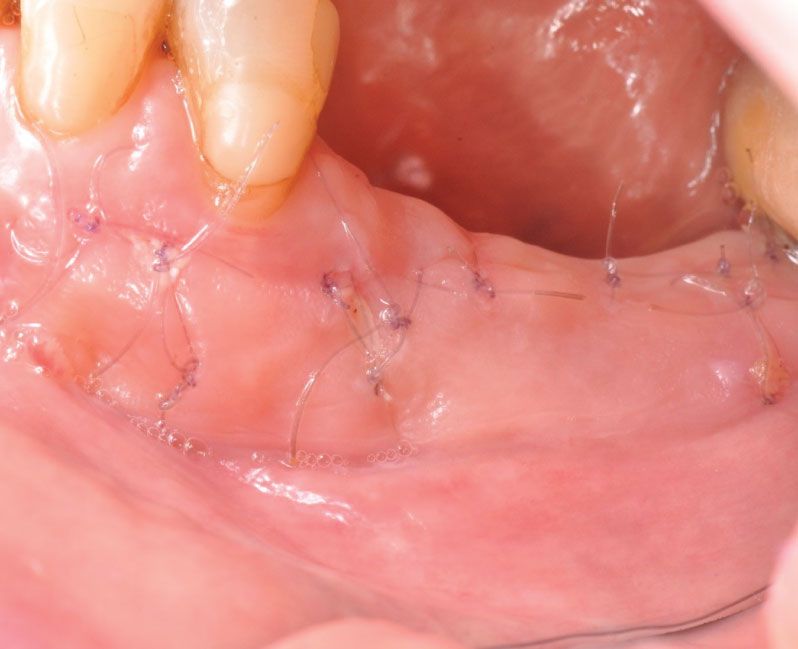

• Réaliser les étapes d’une greffe gingivale : préparation, prélèvement, stabilisation, sutures.

• Techniques de suture (matériau, point simple, point suspendu).